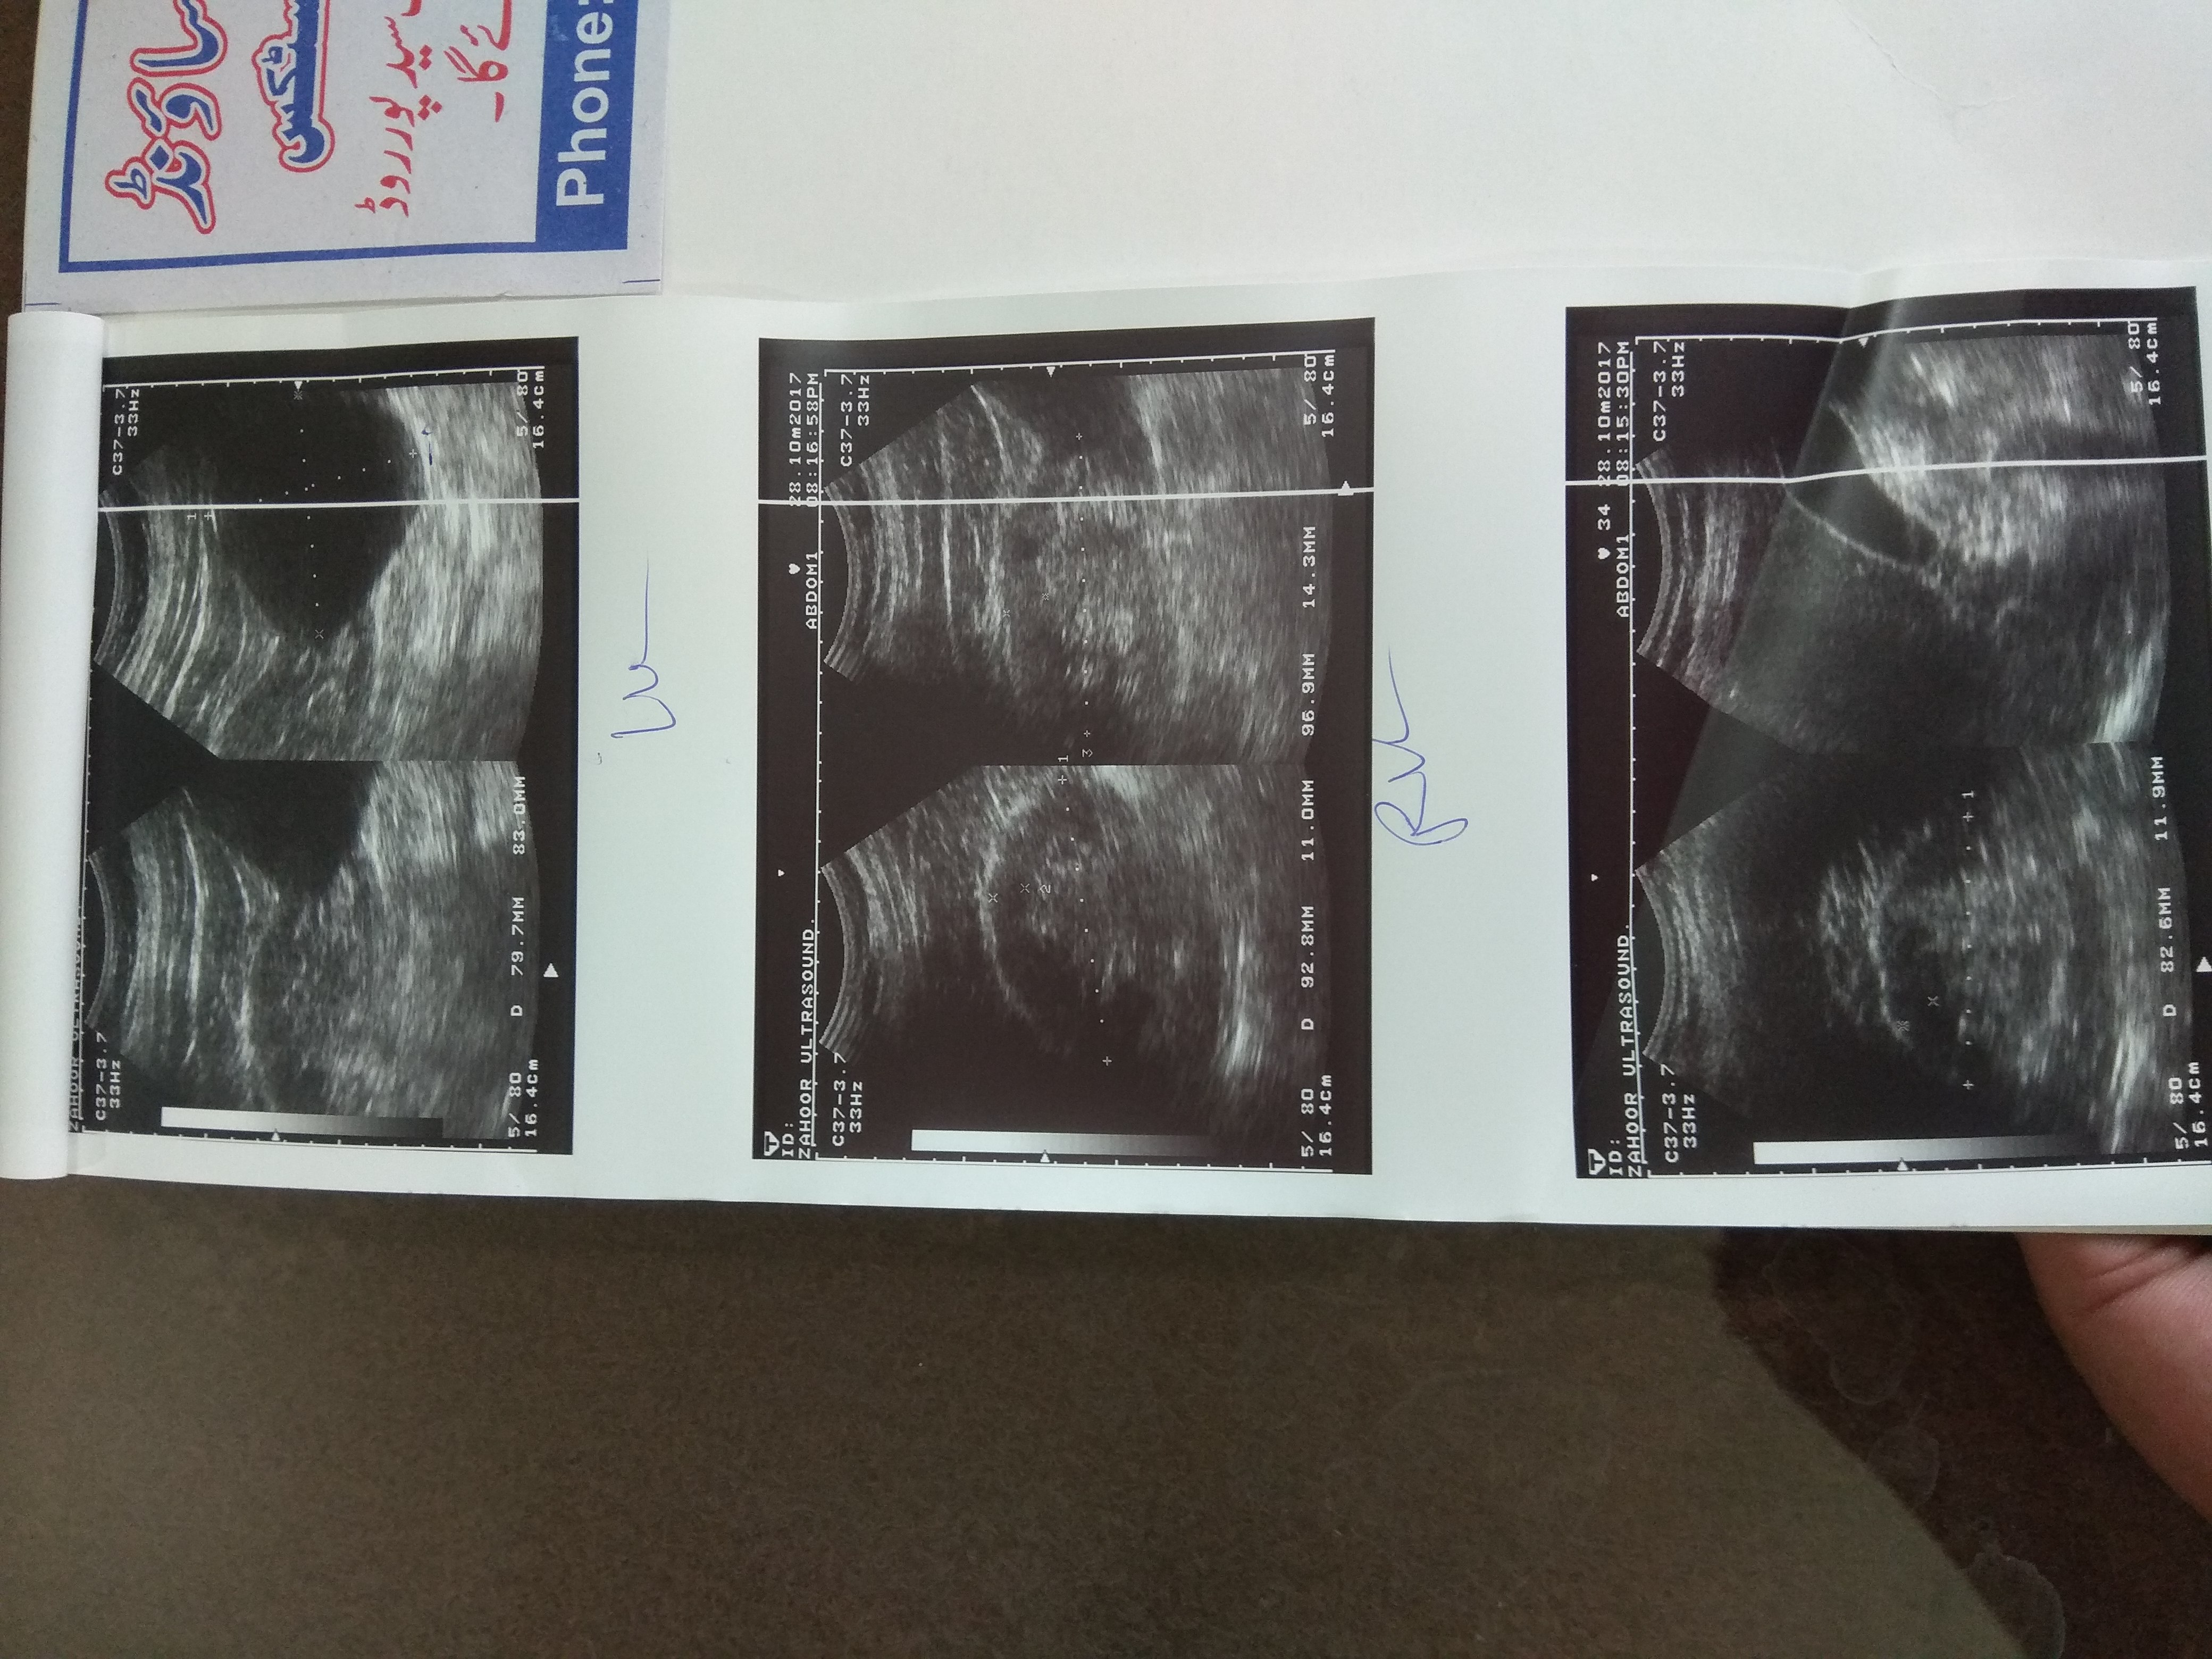

Sir if you have treatment for it somewhere or elsewhere then guide us We are from Rawalpindi. We can come to Lahore or anywhere Reports are attached. Thanks

I think you have an advanced kidney problem and you need to visit kidney doctor for your future management plan .your prescription seems ok but until I see a patient I cannot give suggestions because kidney treatment is an individualized treatment not 1 for all.

Attach Photo here: